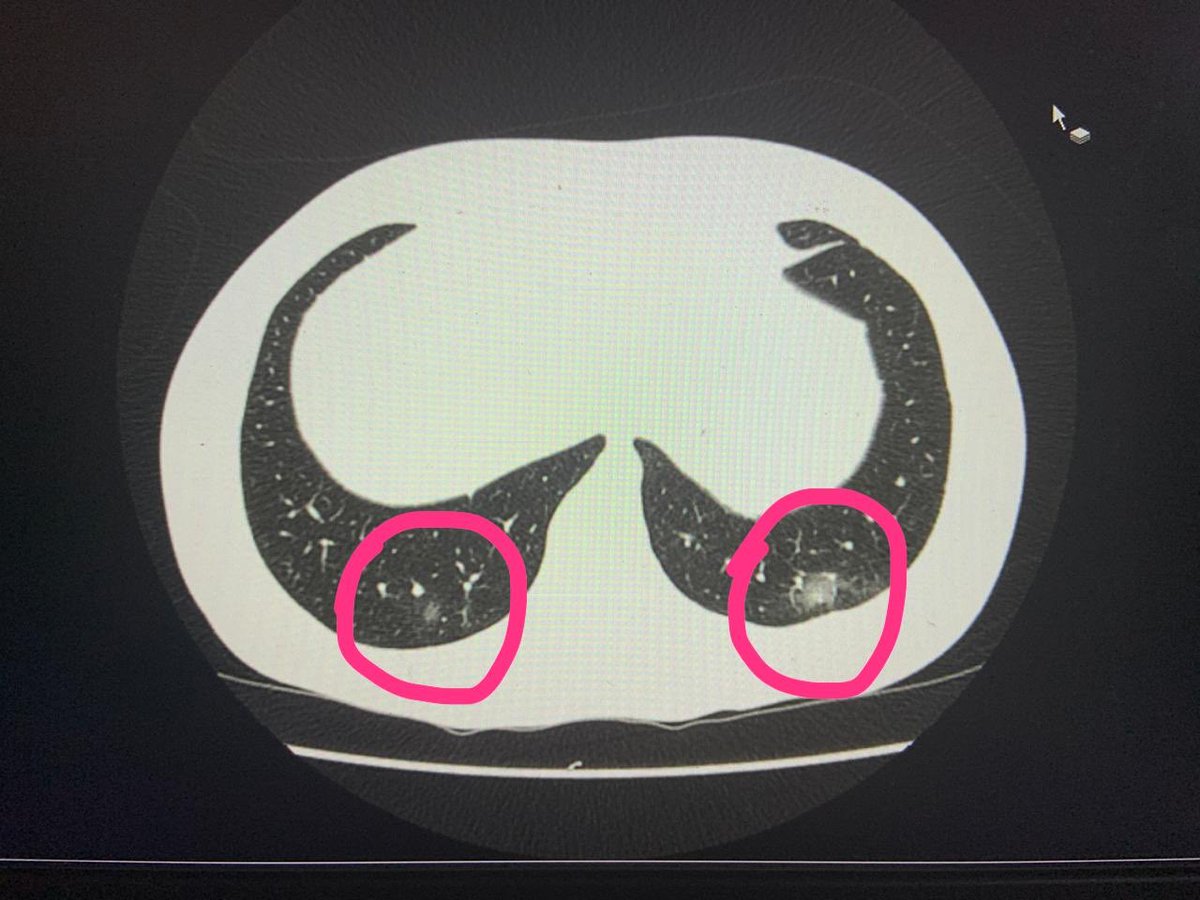

Muita gente chegando no hospital com AVC ou oclusão arterial aguda após quadro de covid.

O exame que pode prever isso é chamdo D-DIMERO.

Meu D-DIMERO deu aumentado.

Daí além do coquetel pra COVID, com antibiótico e medicações sintomáticas, tive que tomar anticoagulante pra evitar eventos pró-trombóticos.